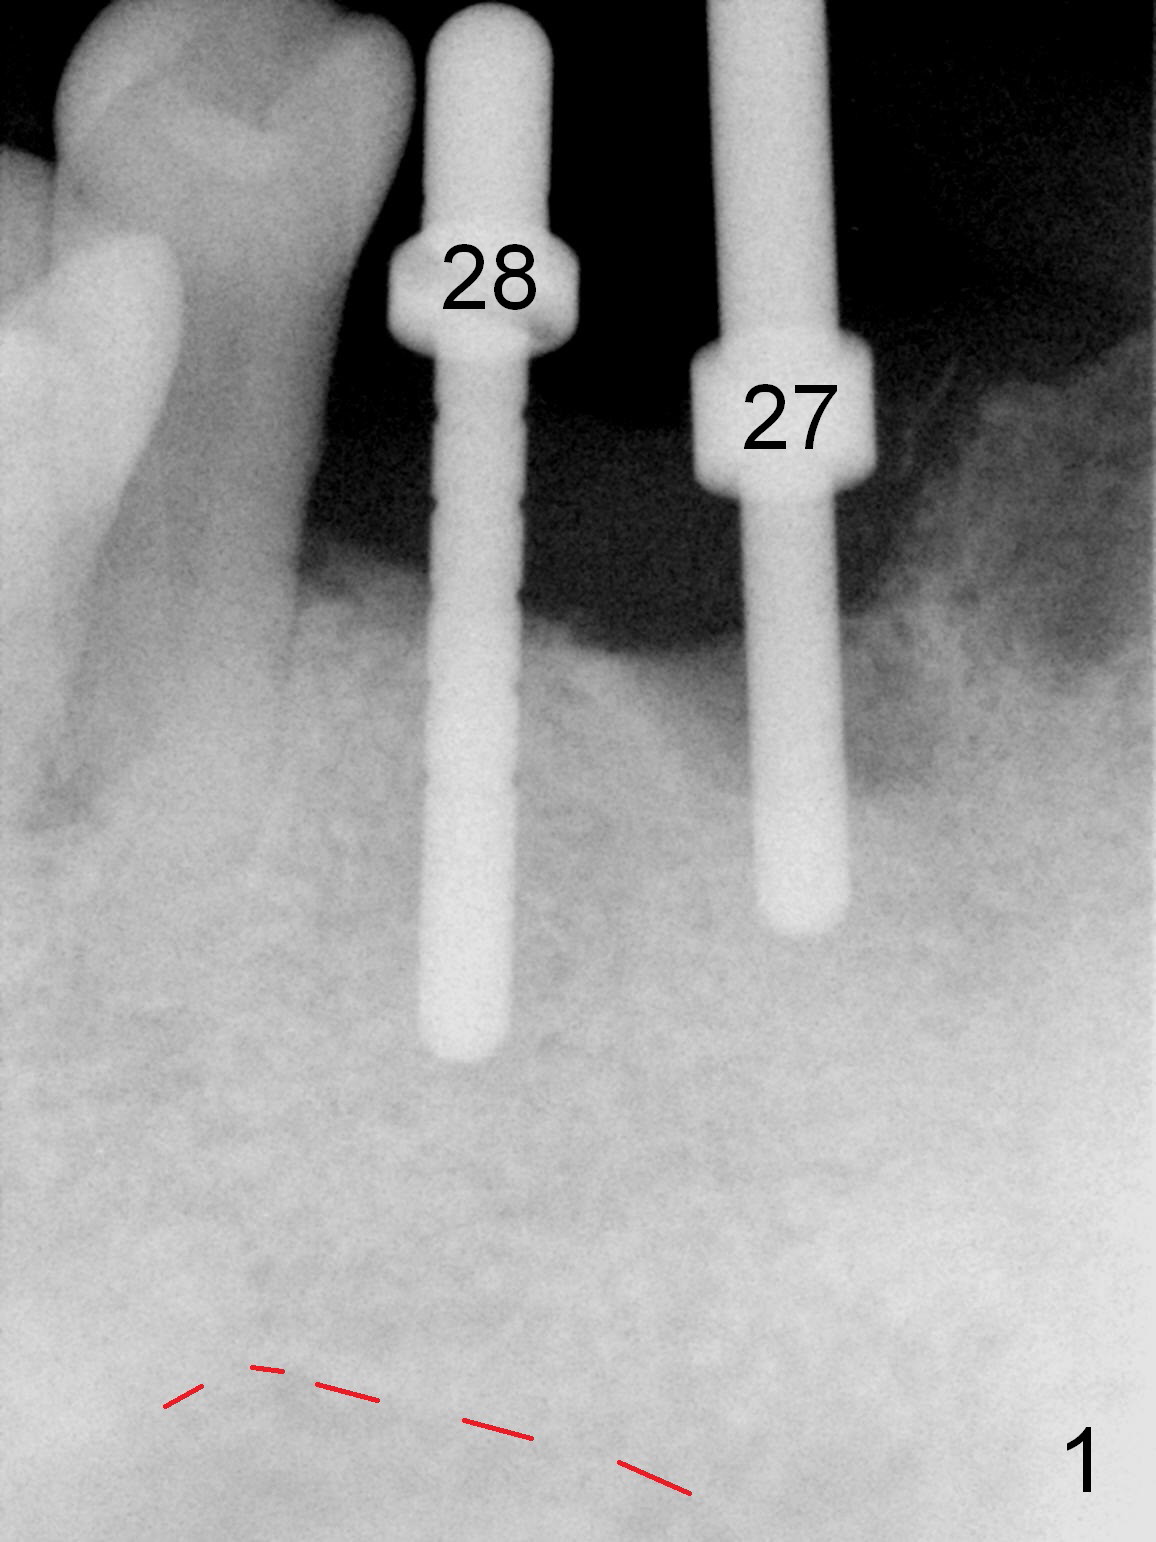

As expected, the bone density in the mandibular anterior region is found to be high during initial osteotomy (Fig.1-3). Five implants are placed at the sites between #22 and 28 (Fig.4,5): 3x14(2) mm 1-piece (bone-level) implants in the incisor region; 4.5x17 mm 2-piece (tissue-level) ones in the canine/premolar area. All of the implants are placed as lingual as possible. Bone graft is placed (*). Red dashed line: the superior border of the Inferior Alveolar Canal. Immediate splinted provisional bridge is fabricated. One week postop, periodontal dressing remains attached to the provisional and the gingiva.